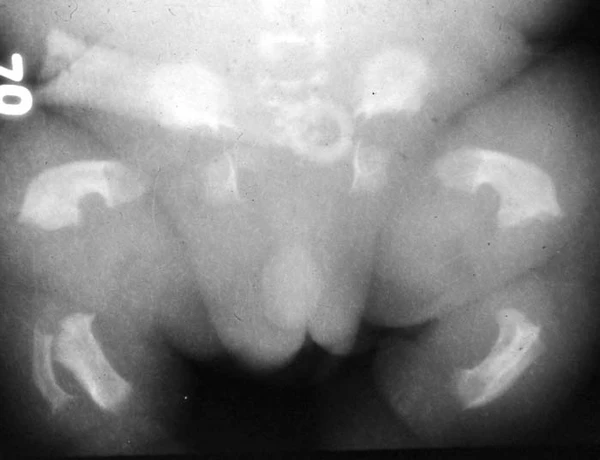

Танатофорная дисплазия проявляется при рождении выраженными диспропорциями скелета и характерными черепно-лицевыми, неврологическими и соматическими особенностями. У новорождённых отмечается относительная макроцефалия с крупным родничком, выступающим лбом, уплощённой переносицей и иногда экзофтальмом. Длина туловища обычно остаётся в пределах нормы, при этом конечности резко укорочены с избыточными кожными складками. Грудная клетка узкая с укороченными рёбрами и выпяченным животом. Пальцы рук короткие. Для I типа характерны изогнутые бедренные кости, для II типа — более прямые бедренные кости и череп в форме трилистника вследствие краниосиностоза[2][6].

- Пренатальная ультразвуковая диагностика — в I триместре выявляется выраженное укорочение трубчатых костей, макроцефалия, расширение воротникового пространства, гипоплазия грудной клетки, двусторонняя косолапость. Во II—III триместре наблюдается задержка роста, узкая грудная клетка с короткими рёбрами, платиспондилия, вогнутые (по типу «телефонной трубки») бедренные кости, череп в форме трилистника, гидроцефалия, аномалии височных долей, относительная макроцефалия[3][8][9].

- Рентгенологическое исследование — наблюдается ризомелическое укорочение костей, неровные метафизы, платиспондилия, сужение большого затылочного отверстия, вогнутые бедренные кости или клеверообразная форма черепа, признаки компрессии ствола мозга[3][6].